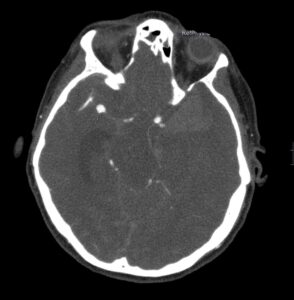

Angio-TC craneal